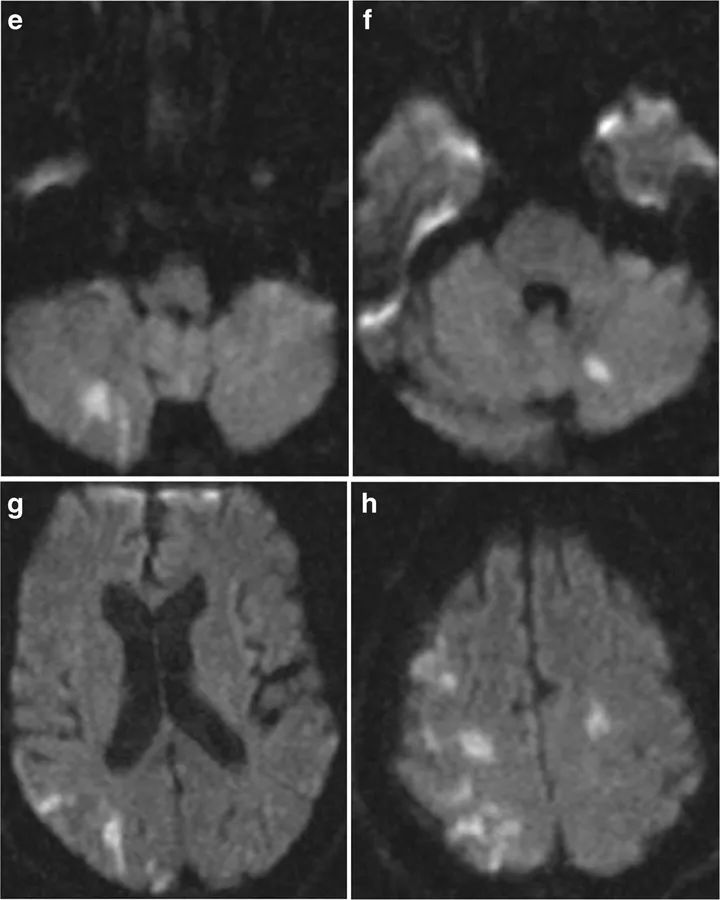

图1 62岁男性,突发左侧偏瘫87分钟后完成了CT扫描,但CT上并未检测出患者的细胞毒性脑水肿,小脑半球上两个微小的病变并不能对症状做出解释(a~d)。症状发作后3小时10分钟,患者完成了MRI扫描,DWI显示患者大脑和小脑半球呈现出多发栓塞形式的小病灶,大脑半球右侧为著,这解释了患者的卒中症状(f~h)。经进一步检查,本例患者有主动脉夹层。